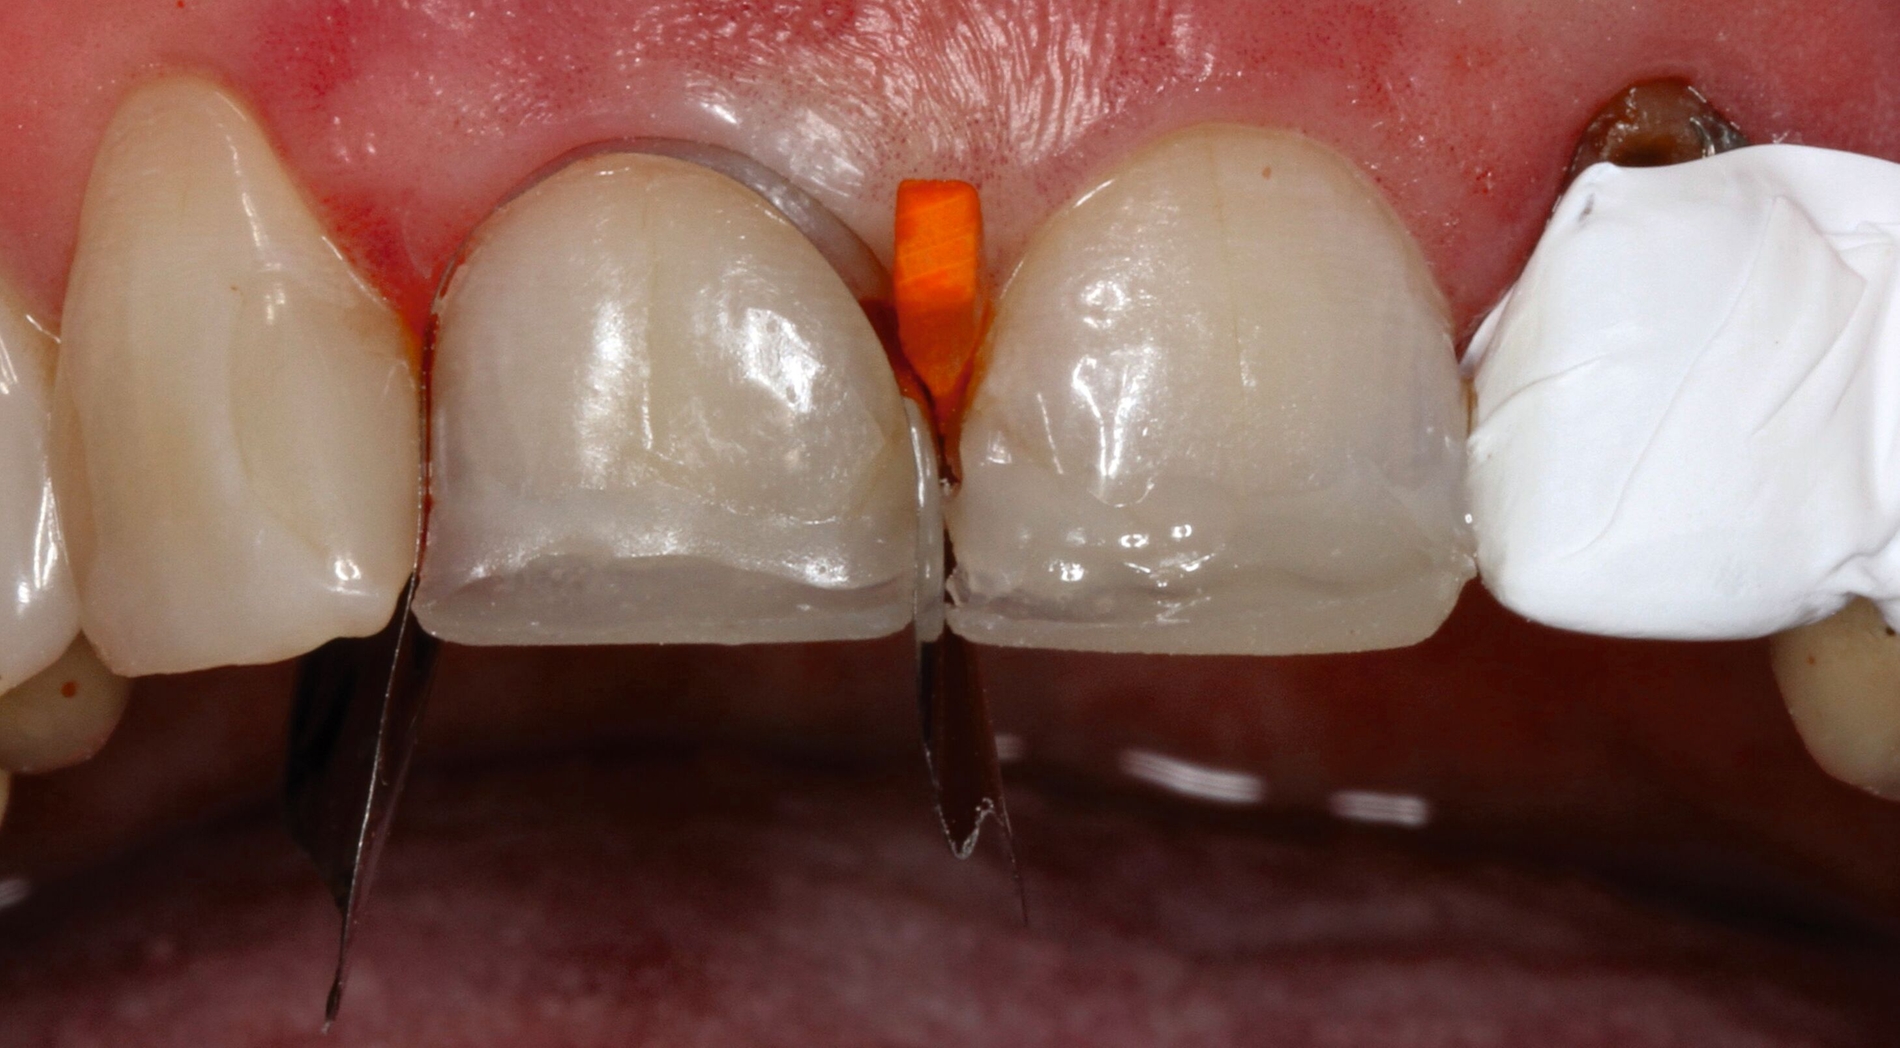

Direkte Kompositveneers an Zahn 11 und 21

Nach Herstellung eines Wax-ups wurde zur Visualisierung des erzielten Ergebnisses und zur Kontrolle der Funktion ein intraorales Mock-up angefertigt (Abbildungen 4a bis 4d). Zur definitiven Versorgung wurden die Zähne 11 und 21 mit einem Universaladhäsiv im Etch & Rinse-Modus unter Verwendung eines Silikonschlüssels als Formhilfe sowie der Anlage von Frontzahnmatrizen (Unica anterior) mit direkten Kompositveneers in Inkrementschichttechnik restauriert (Abbildungen 4e bis 4g). Auf eine Gingivektomie zur Harmonisierung der Rot-Weiß-Ästhetik der elongierten Zähne 11 und 21 wurde auf Wunsch des Patienten verzichtet.

-> Der Vorteil der gewählten Frontzahnmatrizen liegt in der optimalen Visualisierung der finalen Form der Restauration und in der adäquaten Gestaltung der interproximalen Kontakte und zervikalen Ränder durch Gingivaretraktion [Urkande et al., 2023; Amaro et al., 2021].